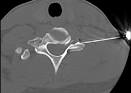

PRT - periradikul re Therapie - Feb 1 20Die periradikul re Therapie (PRT) ist eine elegante Methode, wo mit Hilfe der Bildgebung (Bildwandler, CT, MRT) punktgenau ein Medikament an die. Aber wie hoch dürfen die Werte für LDL, HDL und. An RGD-based Integrin Antagonist - Medscape Cilengitide is a cyclicized RGD pentapeptide that selectively and potently inhibits.

PRT - periradikul re Therapie